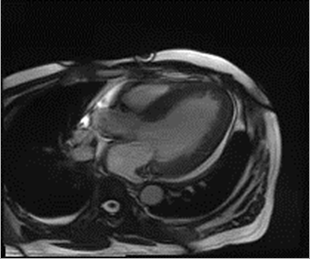

图2.心脏彩超左室壁均匀性增厚

2月前,一名50岁男性患者因反复活动后气促半年,加重2月来到心内二科住院,患者爬楼或快步行走时即感气促,伴胸闷,休息后缓解,无胸痛、心悸、黑朦、晕厥。2月前上述症状较前加重,活动耐量下降,无夜间阵发性呼吸困难。2017年诊断“重度阻塞性睡眠呼吸暂停低通气综合征”,使用无创呼吸机治疗。有猝死家族史,其父亲及兄弟姐妹中3人于50岁左右猝死。入院查NT-proBNP 2761.02 pg/ml↑,余住院患者常规实验室检验指标未见异常。心脏彩超双房增大,心肌弥漫性增厚并室壁运动幅度广泛减弱(室间隔15mm、左室后壁17mm),心功能参数减低LVEF 41%(辛普森法),少量心包积液。而心电图肢体导联及左胸壁导联QRS波低电压,这与肥厚型心肌病常伴心电图高电压的特征不匹配。